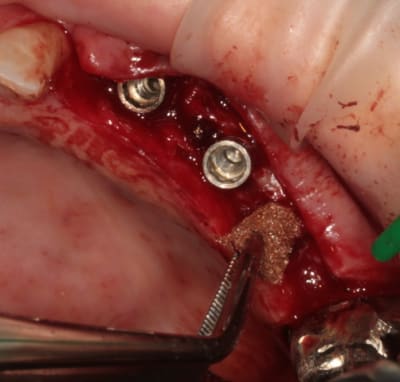

mise en place du conique lisse

L'outil de CLIO

contrôle, axe et profondeur

et un et deux et trois

D1 pour "assouplir"

éponge

implant lisse conique

éponge...